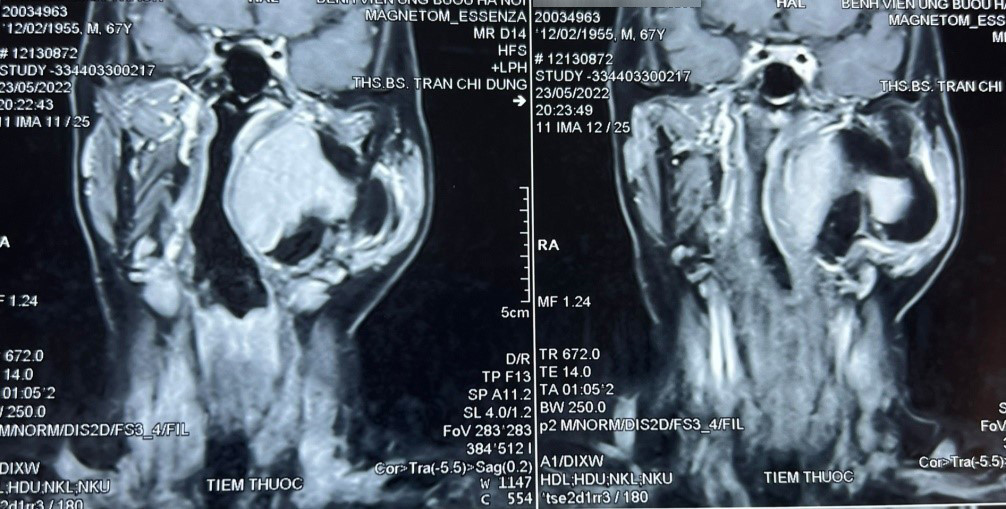

Bệnh nhân đến khám vì khối sưng phồng vùng mang tai trái, không kèm theo khó chịu hay đau đớn. Qua thăm khám, bác sĩ phát hiện một khối u lớn vùng cổ kích thước khoảng 10 x 8 cm, thuộc khoảng bên họng, trải dài từ nền sọ xuống hạ họng, đẩy lệch thành bên họng vào trong. Khối u gồm 2 phần, phần nông nằm dưới tuyến mang tai và phần còn lại nằm sâu hơn.

Chẩn đoán sơ bộ ban đầu cho thấy khối u là lành tính, ranh giới không rõ ràng. Thông qua hội chẩn các bác sĩ quyết định tiến hành phẫu thuật sớm lấy bỏ khối u tránh nguy cơ khối u chèn ép vào đường thở, đường ăn, thần kinh, mạch máu và các thành phần liên quan khác.